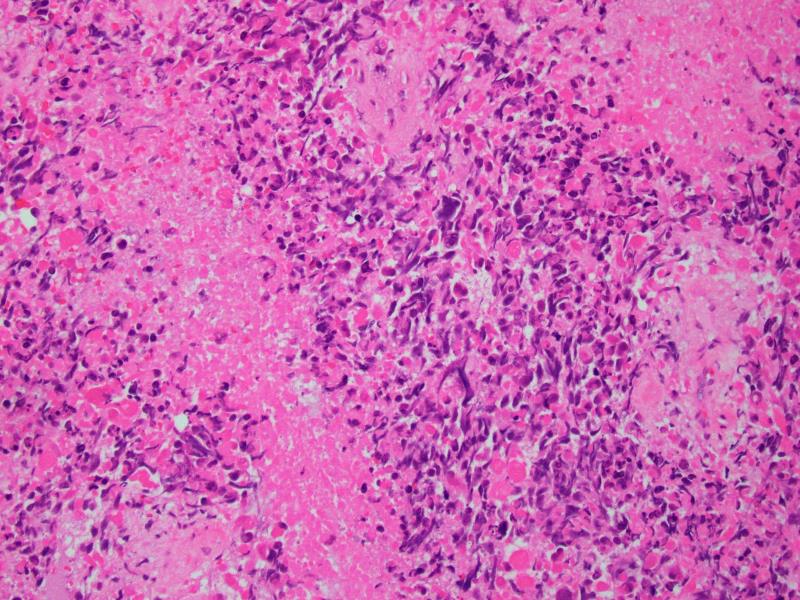

部分区域可见瘤巨细胞或多核巨细胞,类似多形性未分化肉瘤;

肿瘤内常见坏死灶,核分裂象活跃。

镜下见肿瘤由异型性明显的圆形、多边形深嗜酸性的细胞和一些小的未分化细胞及梭形细胞混合组成;